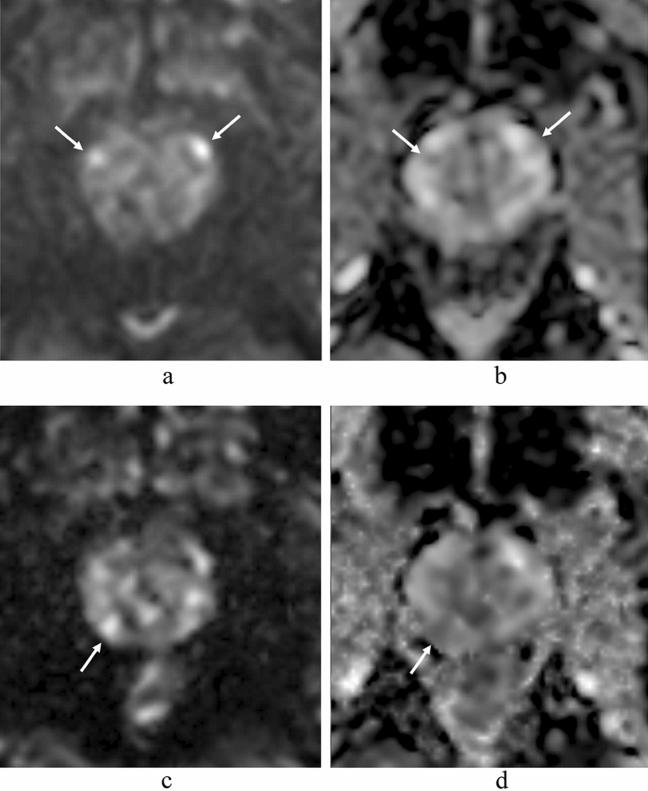

在 3.0T 下比较单激发 EPI 和多激发 EPI 在前列腺 DWI 中的应用。

Comparison of single-shot EPI and multi-shot EPI in prostate DWI at 3.0 T.

In prostate MRI, single-shot EPI (ssEPI) DWI still suffers from distortion and blurring. Multi-shot EPI (msEPI) overcomes the drawbacks of ssEPI DWI. The aim of this article was to compare the image quality and diagnostic performance for clinically significant prostate cancer (csPC) between ssEPI DWI and msEPI DWI. This retrospective study included 134 patients with suspected PC who underwent 3.0 T MRI and subsequent MRI-guided biopsy. Three radiologists independently assessed anatomical distortion, prostate edge clarity, and lesion conspicuity score for pathologically confirmed csPC. Lesion apparent diffusion coefficient (ADC) and benign ADC were also calculated. In 17 PC patients who underwent prostatectomy, three radiologists independently assessed eight prostate regions by DWI score in PI-RADS v 2.1. Anatomical distortion and prostate edge clarity were significantly higher in msEPI DWI than in ssEPI DWI in the three readers. Lesion conspicuity score was significantly higher in msEPI DWI than in ssEPI DWI in reader 1 and reader 3. Regarding discrimination ability between PC with GS ≤ 3 + 4 and PC with GS ≥ 4 + 3 using lesion ADC, AUC was comparable between ssEPI DWI and msEPI DWI. For diagnostic performance of csPC using DWI score, AUC was comparable between msEPI DWI and ssEPI DWI in all readers. Compared with ssEPI DWI, msEPI DWI had improved image quality and similar or higher diagnostic performance.

摘要

在前列腺 MRI 中,单次激发 EPI(ssEPI)DWI 仍然存在失真和模糊的问题。多激发 EPI(msEPI)克服了 ssEPI DWI 的缺点。本文旨在比较 ssEPI DWI 和 msEPI DWI 对临床显著前列腺癌(csPC)的图像质量和诊断性能。这项回顾性研究纳入了 134 名疑似 PC 患者,他们均接受了 3.0T MRI 检查和随后的 MRI 引导活检。三位放射科医生独立评估了病理证实的 csPC 的解剖失真、前列腺边缘清晰度和病灶显影评分。还计算了病灶表观扩散系数(ADC)和良性 ADC。在 17 名接受前列腺切除术的 PC 患者中,三位放射科医生通过 PI-RADS v 2.1 对 8 个前列腺区域的 DWI 评分进行了独立评估。三位读者均认为 msEPI DWI 的解剖失真和前列腺边缘清晰度明显高于 ssEPI DWI。读者 1 和读者 3 认为 msEPI DWI 的病灶显影评分明显高于 ssEPI DWI。对于使用病灶 ADC 区分 GS≤3+4 和 GS≥4+3 的 PC,ssEPI DWI 和 msEPI DWI 的 AUC 相当。对于使用 DWI 评分诊断 csPC 的性能,所有读者均认为 msEPI DWI 和 ssEPI DWI 的 AUC 相当。与 ssEPI DWI 相比,msEPI DWI 的图像质量得到了改善,且诊断性能相似或更高。